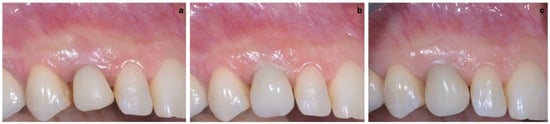

2.3. Provisional Restoration

As shown in Figure 13, the maturation of soft tissue at 1 month (a), 3 months (b) and 6 months (c) after surgery was evident. The peri-implant soft tissues were conditioned with the provisional crown until the shape and position for the mucosal scallop to resemble the gingival margin of the adjacent corresponding tooth and the progressive growth of peri-implant papillae were obtained [19]. In this phase, the patient was called every 2 weeks for us to check the provisional restoration. At the end of the conditioning phase, it was possible to place the definitive, screw-retained restoration (Figure 14a–c).

Figure 13. Maturation of soft tissue at 1 month (a), 3 months (b) and 6 months (c) after surgery.